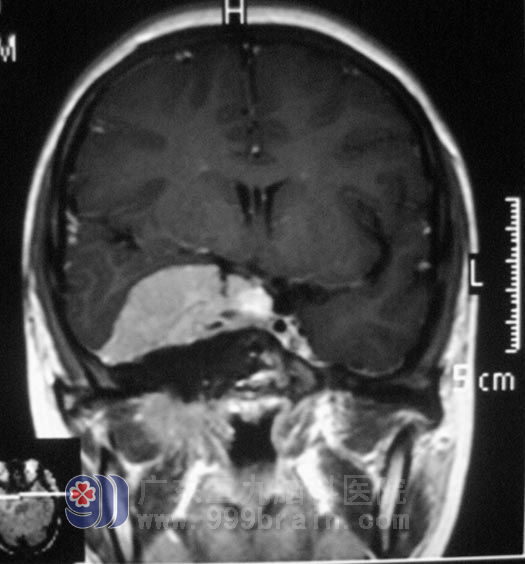

小李在2008年高考那年,出现右眼视力下降,以为是高负荷的复习迎考,造成视力出现问题。一年前右耳听力开始进行性下降,前十多天又出现了右耳失聪,外院行头颅MR检查提示:右侧眶内、中颅窝底、岩斜区占位,病变大小4.98cm×3.34cm×2.62cm,主要位于中颅窝,小部分累及后颅窝,脑干受压。

广东三九脑科医院综合神经外科 鲁明主任查阅影像资料发现:肿瘤侵润海绵窦,颅内外沟通,经CT检查见蝶骨及斜坡右侧、右侧颞骨岩部、额骨底部右侧骨质异常,经耳鼻喉科活检排除鼻咽癌。